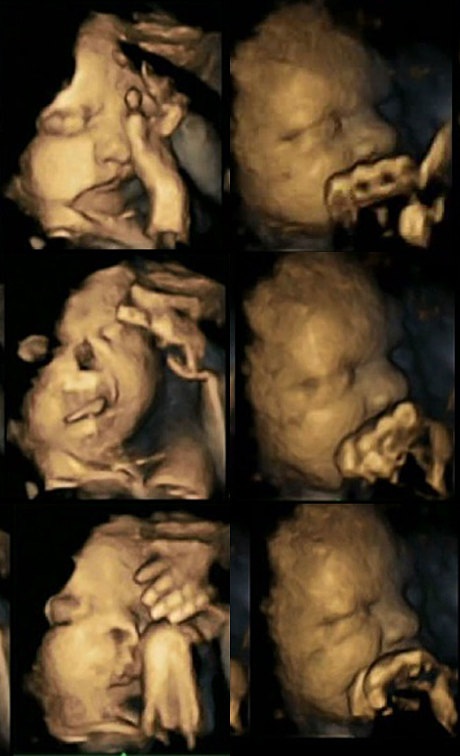

Thai nhi nằm trong bụng một người mẹ đang hút thuốc (trái) có dấu hiệu chuyển động miệng liên tục và đưa tay lên vuốt mặt nhiều đáng kể so với thai nhi nằm trong tử cung một người mẹ không hút thuốc (phải).

Thai nhi trong bụng người mẹ hút hơn 14 điếu thuốc mỗi ngày (trái) so với hình ảnh thai nhi trong bụng bà mẹ không hút thuốc.

Sau khi nghiên cứu hình ảnh quét của thai nhi lúc 24, 28, 32 và 36 tuần, Nadja nhận thấy rằng thai nhi trong bụng những người mẹ hút thuốc thường xuyên cử động miệng và đưa tay chạm vào cơ thể. Điều này không xuất hiện ở các bé có mẹ không hút thuốc.